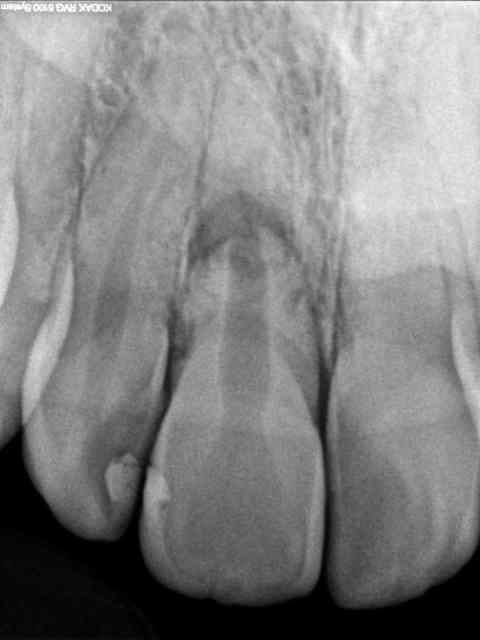

Voici un cliché pris aujourd'hui sur une patiente de 27 ans qui a fracturé la racine de 11 suite à une chute à l'âge de 11 ans.

La dent n'est ni douloureuse, ni mobile, gencive saine mais la teinte de la 11 a virée au gris, ce qui ne gêne pas la patiente qui y est habituée.

La fracture semble être oblique, en bois vert. Un cal a pu se former.

1-obliteration pulpaire du fragment apical=cicatrisation

2-apparement interposition de tissu conjonctif au trait de fracture=pas de risque de resorption

3-dyschromie silencieuse

4-aucune demande esthetique

1+2+3+4=zero intervention

En ce qui concerne le test de vitalité, la dent ne répondait pas au froid.

Où vois-tu une rétraction pulpaire ?...

Par contre, je ne suis pas d'accord avec l'extraction systématique en cas de complication (infection) : si la dent n'est pas mobile à l'heure actuelle, ce n'est pas grâce au fragment apical. Si infection : chirurgie pour retrait du fragment apical + désinfection du fragment coronaire avec bouchon de MTA...et extraction du fragment coronaire seulement si échec.